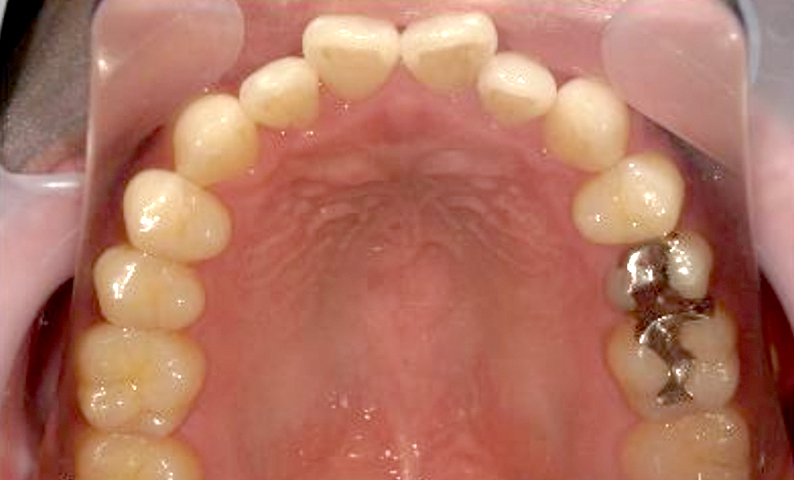

| 治療前 | 治療後 |

|---|---|

|